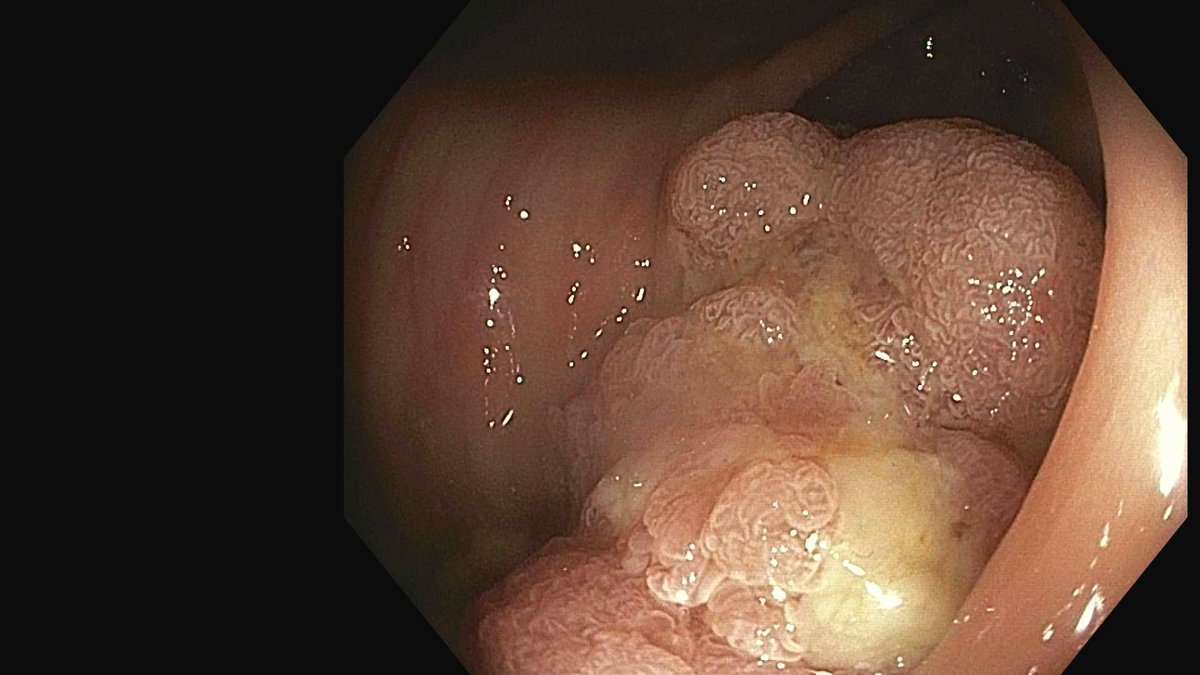

Great example of controlled removal of tissue persistence with EndoRotor in the cecum. Precise vacuum that can be increased or decreased based on tissue response is a key contributor to our low adverse event rate. #endoscopy #innovationinhealthcare #EndoRotor

English